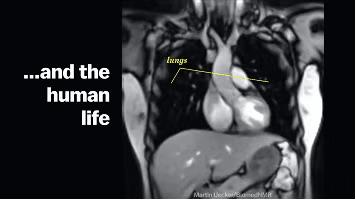

肺部变化

另外人的呼吸频率也会加快,血压也会有所上升,身体肌肉会不断收缩,代谢速度加快,耗氧量上升。